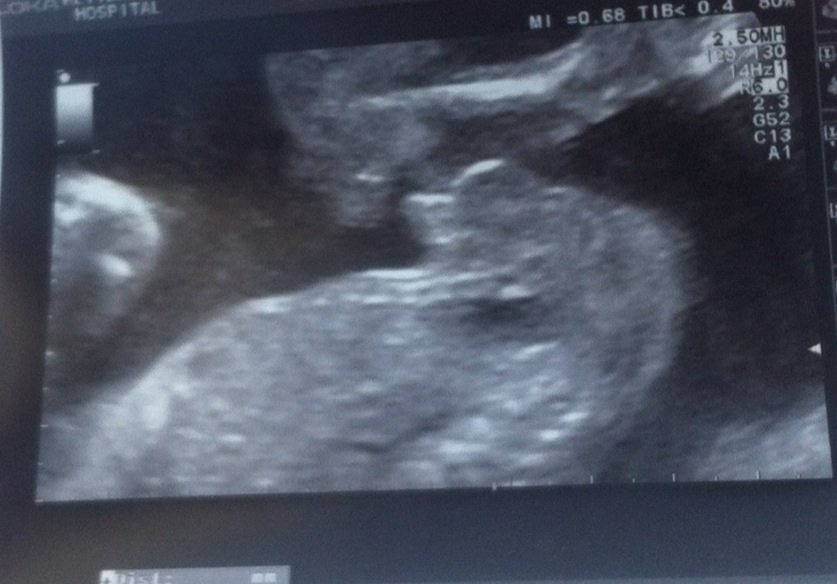

Sonographer says boy, is she right? I'm still in shock lol.